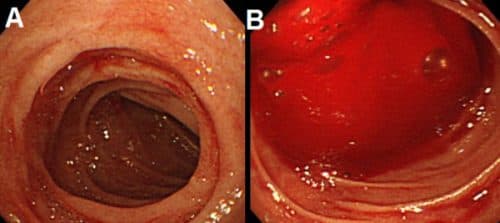

Viêm loét dạ dày chảy máu (hay còn gọi là xuất huyết dạ dày) là một trong những biến chứng nguy hiểm cảnh báo về tình trạng nghiêm trọng của bệnh. Nhận biết sớm các dấu hiệu chảy máu để kịp thời được xử lý và điều trị đúng cách, tránh những hệ quả khôn […]

Bệnh xuất huyết tiêu hóa trên (hay chảy máu đường tiêu hóa trên) là cấp cứu nội ngoại khoa thường gặp hiện nay. Tình trạng này có thể đe dọa đến tính mạng người bệnh nếu không được xử trí kịp thời. Bài viết dưới đây của Hệ thống Y tế Thu Cúc sẽ giúp […]

Xuất huyết tiêu hóa cao (trên) là tình trạng thường gặp ở nhiều người.  Nếu không được phát hiện sớm và điều trị kịp thời, đúng cách, xuất huyết tiêu hóa cao có thể gây nhiều biến chứng nguy hiểm và đe dọa đến tính mạng của người bệnh. Điều trị xuất huyết tiêu hóa […]